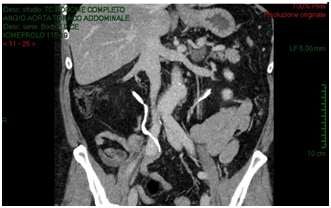

The CT-scan, targeted to a suspect of hemorrhage, did not have delayed phases. Patient received paracentesis with around 3200 cc fluid drained that was sent to microbiological examination. Result of bacteriological exam revealed infection by Proteus Mirabilis and he received target antibiotic therapy with resolution of septic status. In XXII post-operative day, for a progressive increase of serum creatinine we decided to perform an Uro-CT scan. The exam showed reduction of intraperitoneal fluid, right iliac side fluid collection with contrast enhancement during delayed phases; right ureter was not visible under fluid collection (Figure 3). We attempted to insert a ureteral stent in retrograde way but ureter resulted totally interrupted inside the fluid collection so the patient was undergone to explorative laparotomy and toilette of fluid collections. We found ureteral loss of substance of around 3 centimeter localized in anterior ureteral wall. We manufactured end-to-end ureteral anastomosis after positioning of ureteral stent seven French. We removed ureteral stent after 3 months and currently the patient is in follow-up with a good renal function as shown at last CT-scan after 10 months (Figure 4).

Figure 4: After ureteral stent removal, right ureter appears normal ducted with a good kidney function.